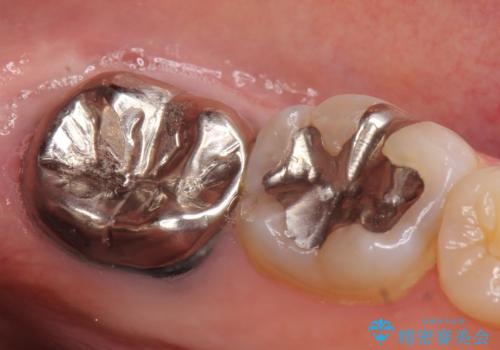

- 左下奥歯でものを咬むと鈍い痛みがあるので診て欲しいといらっしゃった方の症例です。

検査の結果根尖病変(歯根の細菌感染)を認めたため、再根管治療を行いオールセラミッククラウンによる補綴を行いました。